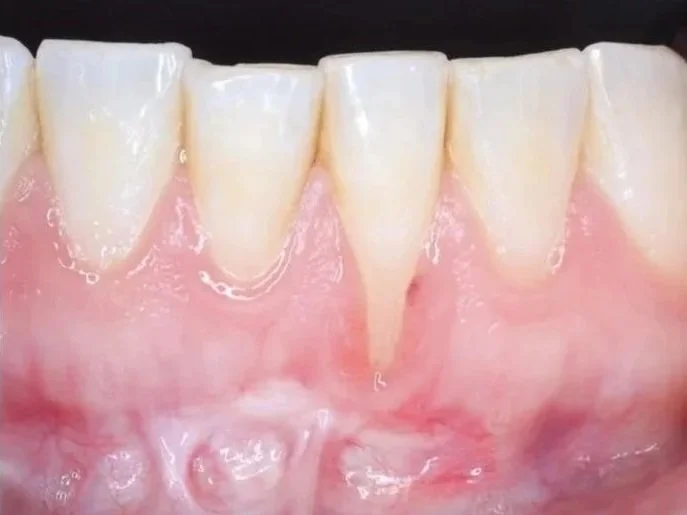

Olika typer av mjukvävnadskirurgi används för att förbättra och stärka skadad eller tunn tandköttsvävnad. Genom att använda mikrokirurgiska tekniker flyttar man tandkött från en del av munnen, oftast gommen, till det utsatta området. Denna behandling hjälper till att återställa ett hälsosamt och starkt tandkött.

- Behandling av blottade tandhalsar och rotytor samt lösningar för estetiska problem kring tänder och implantat.